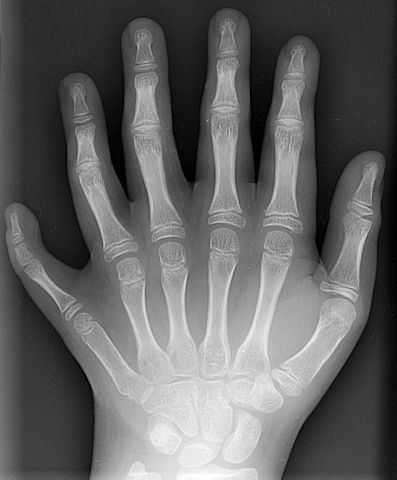

English: Conversion of a DICOM-format X-ray from a patient of en:User:Drgnu23, a ten year old male. This is the patient's left hand, posterior-anterior projection. Identifying tags and such have been stripped. The image is his, released under the GFDL. The image was subsequently altered by en:user:Grendelkhan, en:user: Raul654, and en:user:Solipsist.

Français : Radiographie de la main gauche (projection postérieure-antérieure) d'un jeune patient (10 ans) de Drgnu23 présentant une polydactylie.